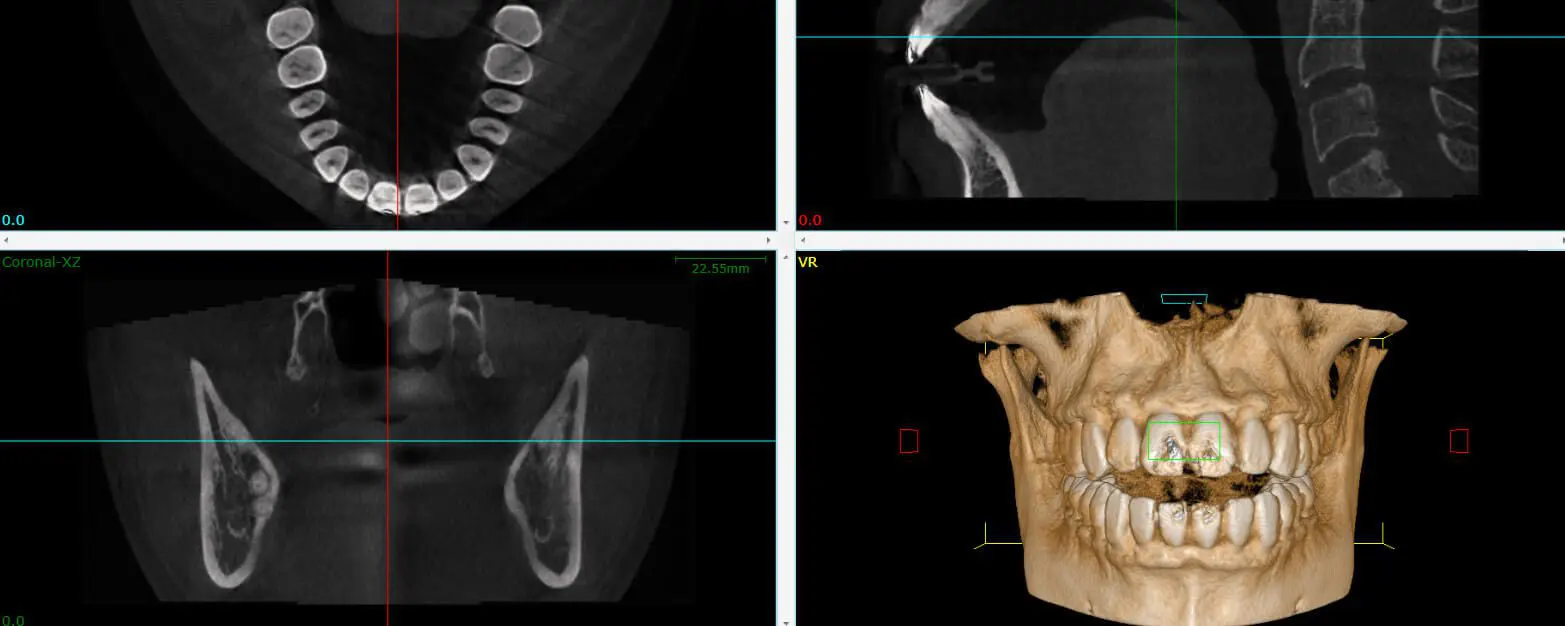

A cone beam CT creates a 3D view and cross sections of the target area. The information it provides is critical for a number of situations, including placing dental implants, performing a complex root canal or extraction, or searching for the source of pain or infection. CBCT gives us the information we need about your condition before a dental procedure.

A cone beam CT circles the head, which overlaps each image or slice, leaving no gaps. The radiation is also much weaker. The most radiation hits the the area of interest, which is where the images overlap to construct the 3D model. This is how CBCT is able to provide a more complete image with less radiation exposure.